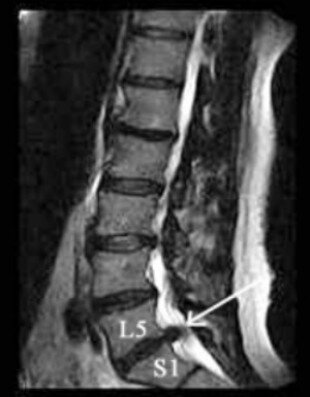

Ciò consentiva una più agevole esecuzione della risonanza magnetica, che evidenziava una voluminosa ernia discale espulsa L5-S1 destra.

Eseguiva 15 sedute di ozonoterapia eco guidata sulla focalità erniaria.

La regressione del dolore è stata lenta e progressiva, con graduale discesa della VAS a 0-1.

Il signore beneficiato di un recupero del contesto familiare, ha potuto riprendere la normale attività lavorativa e sociale e sportiva non agonistica.

A distanza di 4 mesi ha effettuato una nuova risonanza magnetica lombare, che ha documentato la completa scomparsa della voluminosa ernia.

Secondo i criteri della medicina moderna non si può affermare con assoluta certezza che l’ozonoterapia eco guidata sia stata la causa diretta ed esclusiva della scomparsa dell’ernia, tenendo anche conto che la regressione di un’ernia discale può essere un fenomeno naturale e spontaneo.